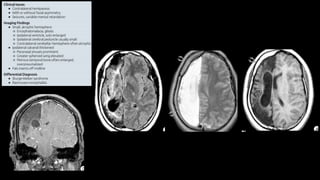

Degeneração corticobasal

• Inclusões TAU em neurônios e na glia

• Atrofia frontotemporal assimétrica

• Áreas motoras e sensoriais

• Preservação do occipital e parietal

• Atrofia e despigmentação da substância nigra

• “alien limb phenomenon”

• Sintomas parkinsoninsmo não respondem ao Levodopa

• Distúrbios cognitivos, linguagem (afasia não fluente)

Putaminal rim; giro pré-frontal e córtex perirolândico;

temporal e occipital preservado